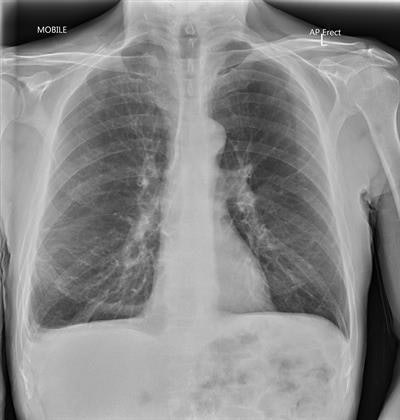

Our radiologists were satisfied with the image quality, with 90% of images taken through glass considered diagnostic. With our parameters, the typical radiation dose to patients is the same whether the x-ray is taken through glass or not.

We have now performed several hundred chest x-rays using this technique. In intensive care unit (ICU) rounds, one radiographer and a nurse tend to stay in the room, while the second radiographer operates the x-ray unit from outside the room. In the emergency department, where the rooms are not as large, staff leave the room while the x-ray is performed. This technique should never be used through lead glass.